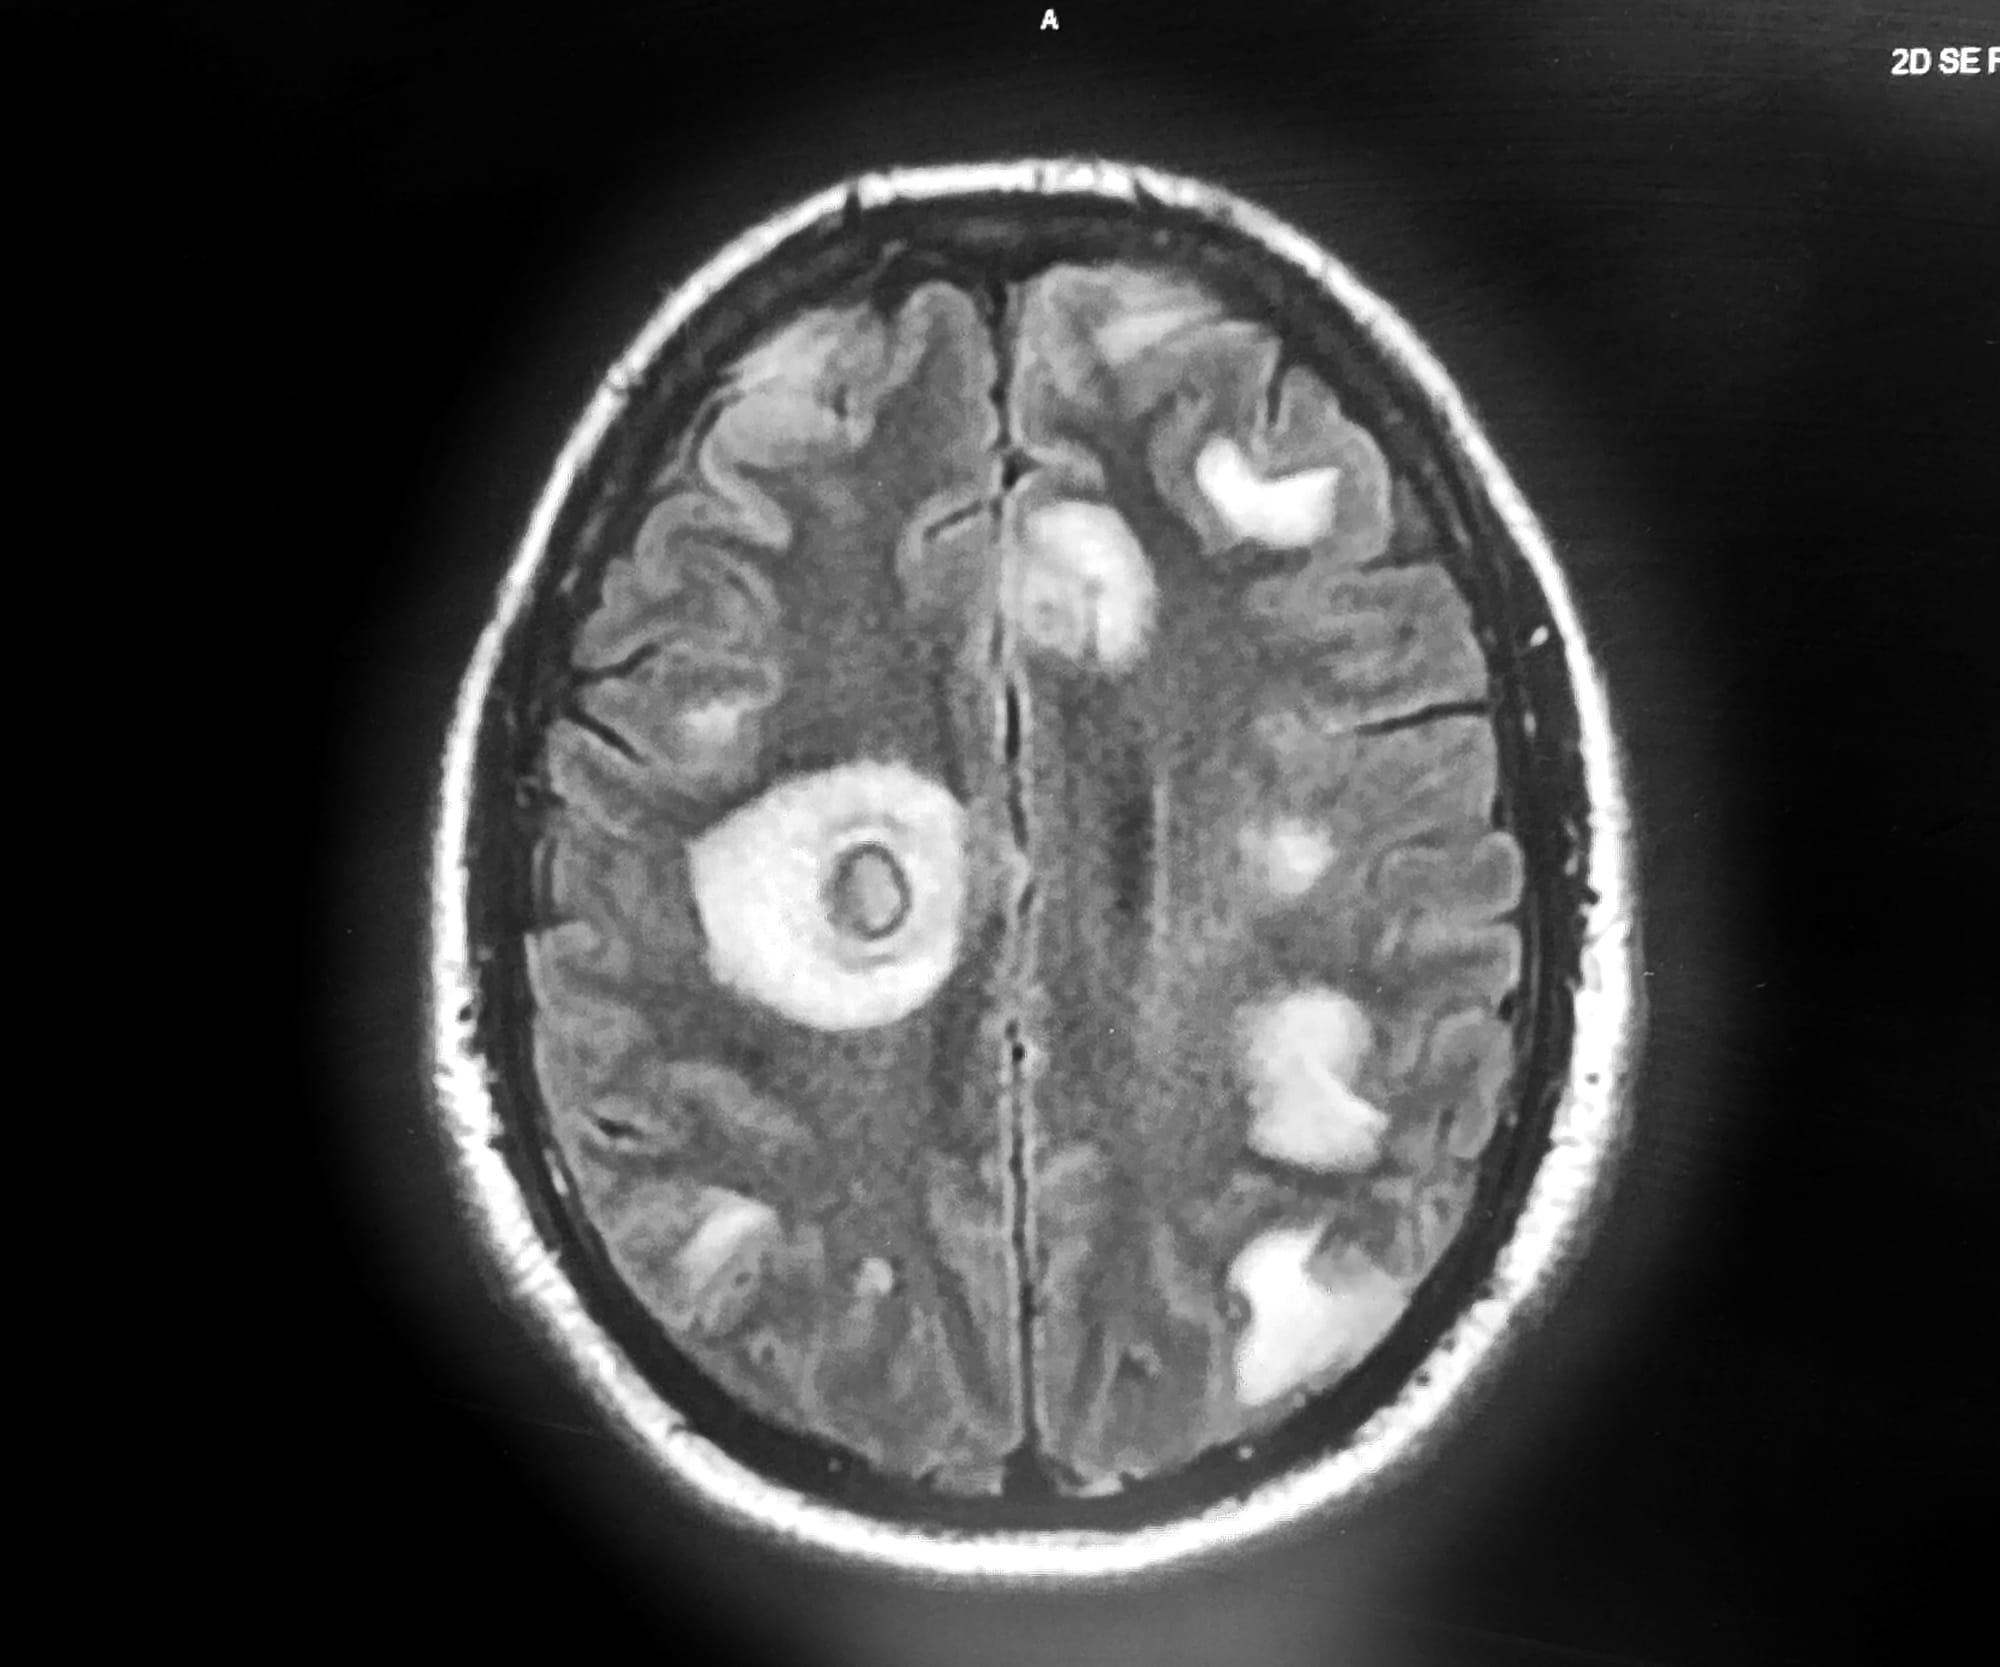

1) Humans do not contract NCC by eating undercooked pork but by ingesting tiny, invisible eggs passed in the stool of humans who harbor adult pork tapeworms in their GI tract. After these eggs enter the environment — often due to poor sanitation and hygiene — they can survive for quite a while and contaminate fresh food and water. After ingestion, either by a human or a pig, the tiny tapeworm eggs then grow into larvae that typically remain inert for years while continuing to grow, especially in the human brain. Finally, sooner or later, the cysts in humans can leak or become inflamed or calcify. That’s when epileptic seizures and other neurologic symptoms typically develop. In the worst case scenario, the enlarging, inflamed cysts can block the passage of spinal fluid within the brain; produce chronic meningitis, visual issues, etc. Or in layman’s terms: confusion, headaches, blindness, seizures — even death. Does RFK have any chronic sequelae from a past bout of NCC or persistent abnormalities on his CT scan? Based on current information, there’s no way to know.

3) Sadly, cysticercosis is far from rare in many parts of the world—especially farming areas in Latin America, Asia, and Africa where humans and pigs are in close contact and sanitation is poor. It’s currently thought that NCC is the world’s most common cause of adult-onset epilepsy. In addition, WHO has identified NCC as a leading cause of death from foodborne diseases.